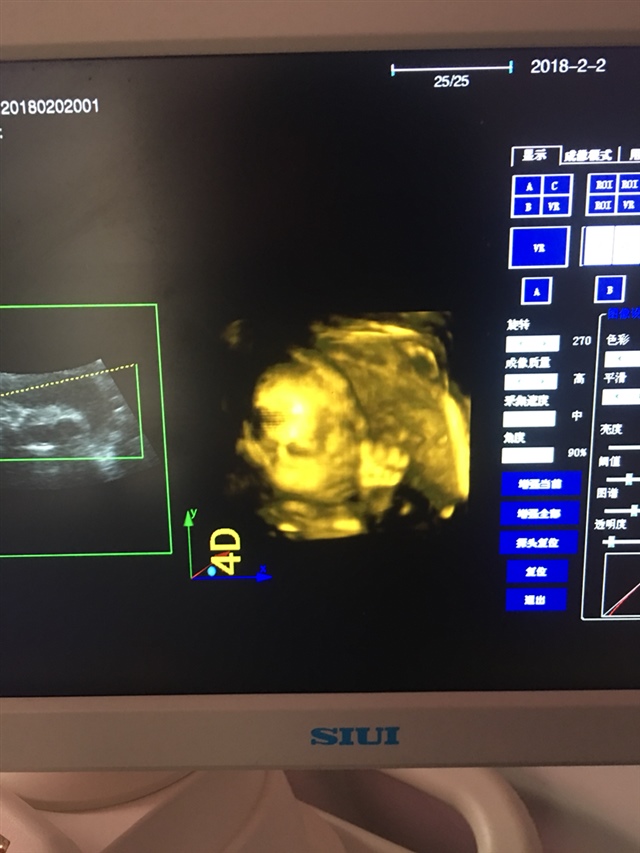

孕33周+2天